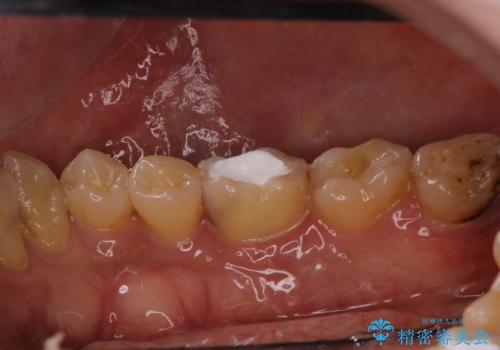

- 1ヶ月前から急に物が当たるだけでも痛いとの事で来院した患者様です。

精密根管治療とオールセラミックで補綴治療を行いました

精密根管治療で痛みはすぐに消退しました。

数ヶ月後には根分岐部の病変もなくなっていました。